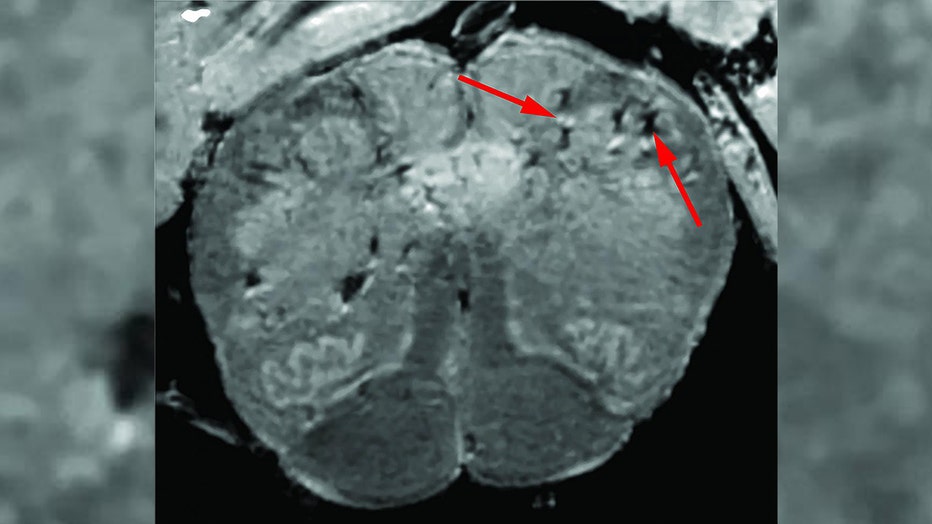

According to a study from the National Institutes of Health published earlier this month, researchers found evidence to suggest that brain damage may be a byproduct of COVID-19. Researchers uncovered blood vessel damage and inflammation in the brains of 19 deceased COVID-19 patients.

"We found that the brains of patients who contract infection from SARS-CoV-2 may be susceptible to microvascular blood vessel damage. Our results suggest that this may be caused by the body’s inflammatory response to the virus," said Avindra Nath, M.D., clinical director at the NIH’s National Institute of Neurological Disorders and Stroke (NINDS).

NIH researchers consistently found blood vessel damage in the brains of COVID-19 patients but no signs of SARS-CoV-2 infections. Arrows point to light and dark spots that are indicative of blood vessel damage observed in the study.